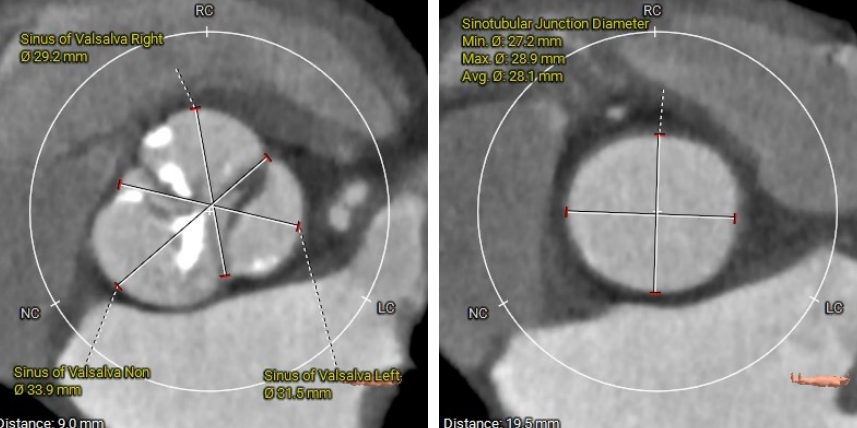

CT测量

主动脉根部CT测量

瓣环周长:74.9mm

LVOT周长:83.1mm

法氏窦三窦直径

左冠状窦:31.5mm;右冠状窦:29.2mm;无窦:33.9mm

STJ高度:19.5mm

升主动脉平均直径:33.8mm

● 主动脉根部:患者主动脉瓣为三叶瓣,左右冠窦可见部分粘连,重度钙化,瓣环到LVOT层面可见钙化,法式窦结构较大,左冠开口高度约11.0mm,右冠开口高度约16.2mm,STJ高度约19.5mm,直径约28.1mm,升主动脉未见明显扩张,心脏角度约49°,左室形态稍小,心肌增厚。